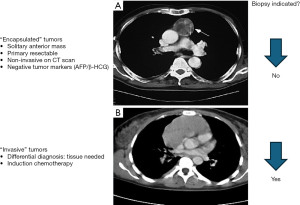

Taking a biopsy of a residual lesion suspicious for lymphoma recurrence on PET imaging following definitive chemo-radiotherapy can be hazardous because of dense mediastinal fibrosis. A core biopsy by opening the fibrotic capsula is needed to sample adequate tissue. Occasionally, the residual mass can be entirely resected by thymectomy to ensure that the residual fluorodeoxyglucose (FDG)-avid zone shown on PET scan is included in the specimen (Figure 3).